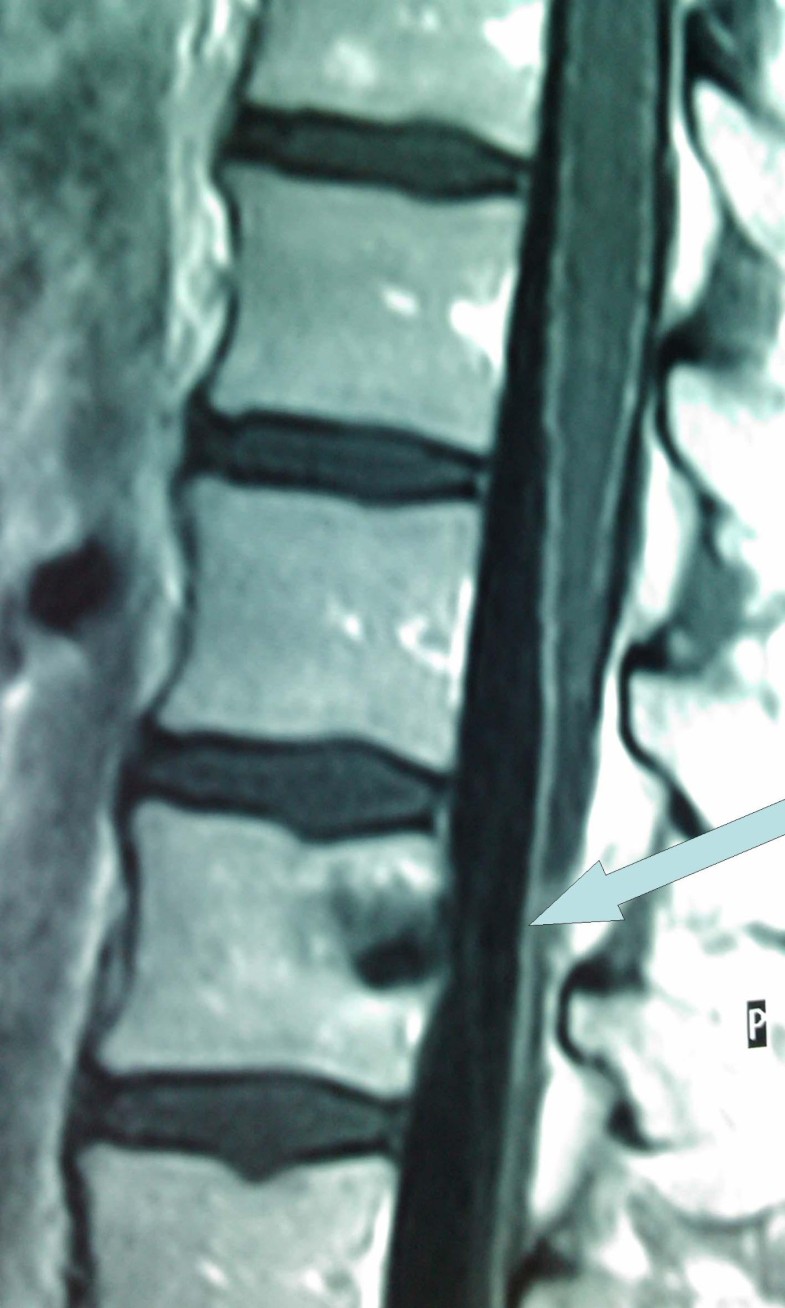

Swordfish bill injury involving abdomen and vertebral column case Swordfish Injuries Swordfish attacks on humans are uncommon, with only a few case reports available in the current literature. The authors report the first known case of a. Swordfish attacks on humans are uncommon, with only a few case reports available in the current literature. Swordfish attacks on humans are uncommon, with only a few case reports available in the current literature.. Swordfish Injuries.

Swordfish bill injury involving abdomen and vertebral column case Swordfish Injuries The authors report the first known. The authors report the first known case of a. Swordfish attacks on humans are uncommon, with only a few case reports available in the current literature. Swordfish attacks on humans are uncommon, with only a few case reports available in the current literature. Giulia manfrini, 36, was riding a wave when the swordfish leapt. Swordfish Injuries.

Swordfish bill injury involving abdomen and vertebral column case Swordfish Injuries Swordfish attacks on humans are uncommon, with only a few case reports available in the current literature. There have been documented cases of serious injury and fatalities after. Swordfish attacks on humans are uncommon, with only a few case reports available in the current literature. Giulia manfrini, 36, was riding a wave when the swordfish leapt out of the water. Swordfish Injuries.